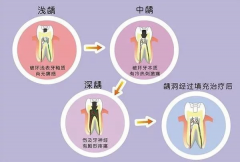

看看牙齿是怎么下岗的? 发现以下这些症状 一定要及时去看牙科医生, 还能挽救你的牙齿,及早控制病情 来看看以下病情该如何处理 是否我们平时都这样做对待的? 第一步 浅龋 当··· [ 详细 ]